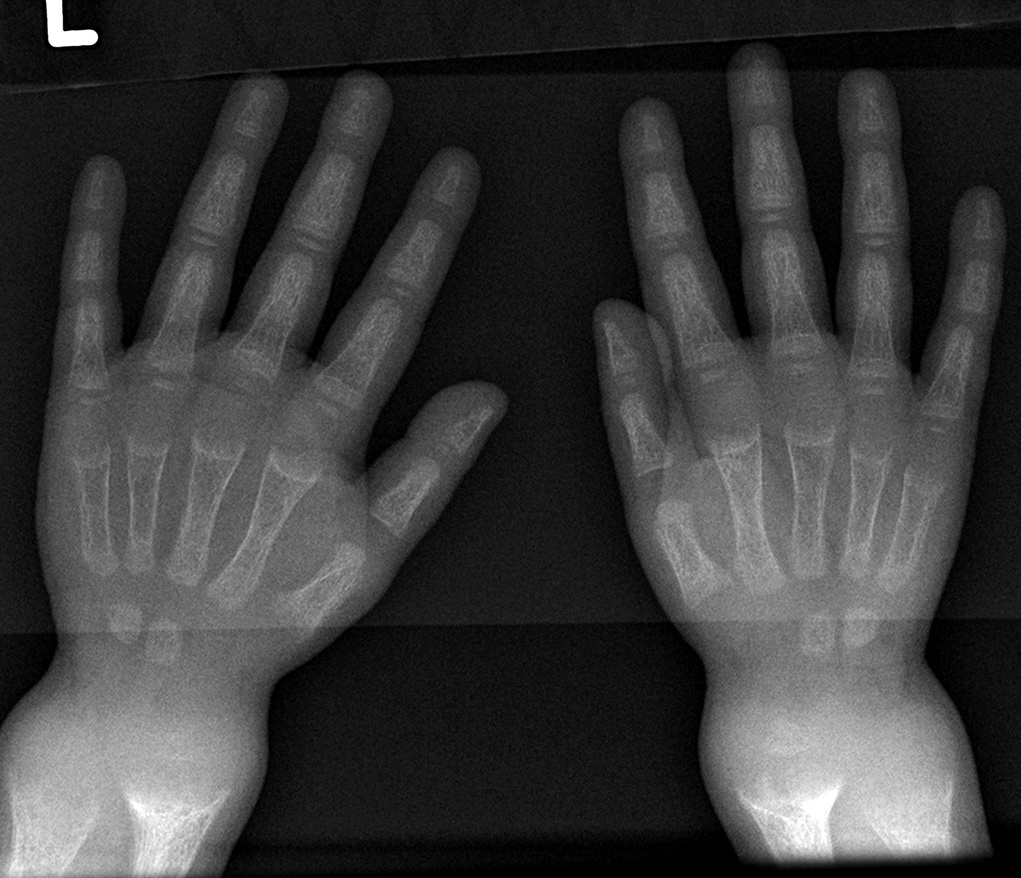

영양 결핍성 구루병의 징후 및 증상으로는 뼈의 압통과 골절, 특히 녹색골절에 대한 취약성이 포함될 수 있다.[14] 영아에게는 두개연화증(부드럽고 얇아진 두개골 뼈)이 나타날 수 있는데,[15][16] 이는 구루병의 첫 번째 징후이다. 두개골 돌출이 나타날 수 있으며 천문의 폐쇄가 지연될 수 있다.

혈중 칼슘 수치가 낮은 저칼슘혈증은 테타니(조절되지 않는 근육 경련)를 유발할 수 있다. 치아 문제도 발생할 수 있다.[14]

- 방사선 사진에서는 일반적으로 석회화되지 않은 골기질로 인해 일시적 석회화 영역이 넓어지는 것을 보여준다. 컵 모양 변형, 섬유화, 골단의 벌어짐은 성장과 지속적인 체중 부하와 함께 나타난다.[47] 이러한 변화는 상완골 근위부, 요골 원위부, 대퇴골 원위부, 경골 근위부와 원위부를 포함한 빠른 성장 부위에서 주로 관찰된다. 따라서 구루병에 대한 골격 전반 검사는 무릎, 손목 및 발목의 전후 방사선 사진으로 수행할 수 있다.[47]